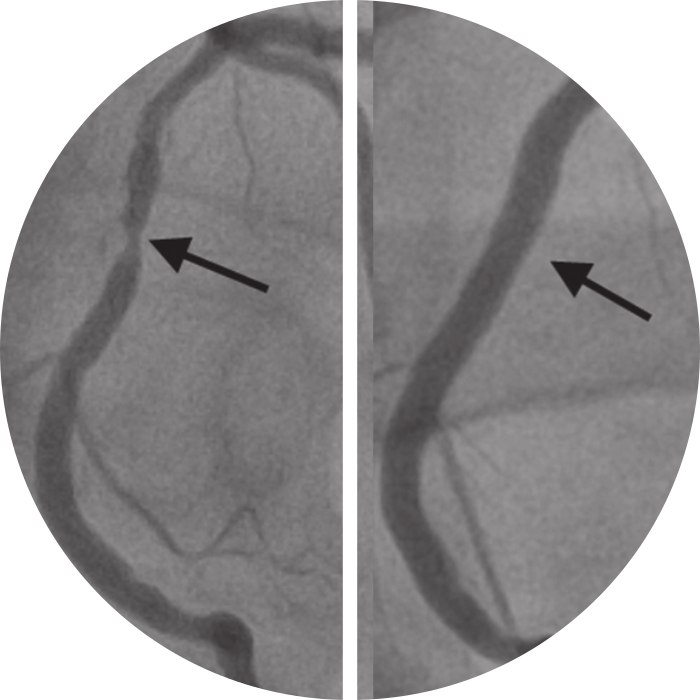

He offers treatment to restore the blood flow & revasularise the foot by doing advanced Endovascular procedures such as peripheral arterial stenting.

Dr. Arun Prasanth and their excellent group of doctors operated on my mother's feet and did endovascular revascularization and stenting and prevented major amputation, even though many other hospitals had said treatment could not be done. God bless.